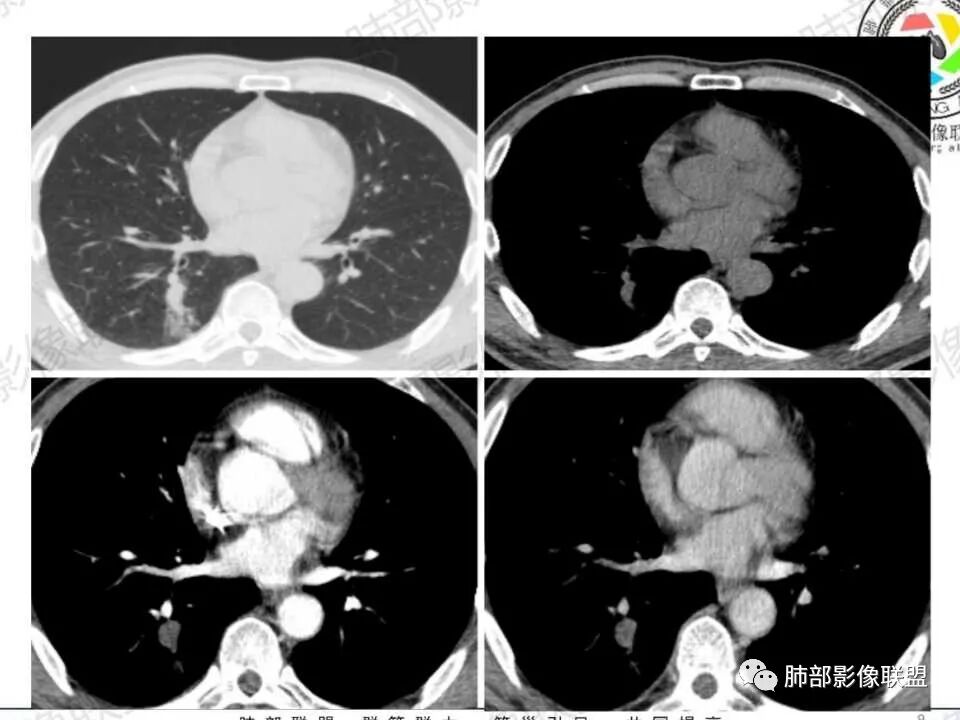

男性病人48岁,既往有糖尿病的病史,影像学表现,右肺下叶后段类圆形的小结节病灶 ,边界比较光整,内见小空洞影 ,病灶远端见小片状的渗出性病灶,增强扫描病灶轻度的强化。病灶在治疗的过程中短期内有增大。整体病灶表现为一个光整结节+远端阻塞性肺炎+小空洞+轻强化,周围无卫星病灶,考虑感染性病变,隐球菌感染?结核次考虑。

右肺下叶结节,边缘光整,密度均匀,伴阻塞炎症,增强无强化,抗感染一周复查效果差,结节内小空洞,阻塞明显,胸膜增厚,糖尿病病史,首先考虑结核,隐球菌待排

糖尿病病史,右肺下叶结节,边缘光整,密度欠均匀,远端阻塞炎症,增强强化不明显,抗感染一周复查,结节较前增大,内出现小空洞,阻塞明显,胸膜增厚,首先考虑结核,隐球菌待排。

3.近背段支气管开口附近结节密度不甚均匀,未见钙化或脂质密度区。边界清楚光整,内侧平直,未见典型深分叶及毛刺,增强扫描轻度强化。

4.哌拉西林、左氧氟沙星等治疗一周后,较大结节影及外围病灶范围均见增大。

5.背段支气管于结节内侧份“旁现侧出”,管壁完整,管腔少量分泌物,近乎疏通状态。结节内隐约出现微小含气空腔。

6.肺门及纵隔未见增大淋巴结。